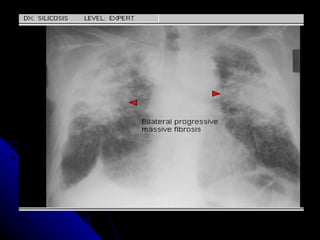

SÍNDROME PARENQUIMAL Conjunto de signos radiográficos que traducen una lesión en el parénquima pulmonar, la  que  puede ser localizada o difusa. Didácticamente podemos dividirlo en tres tipos: Alveolar Intersticial Mixto ( alveolo intersticial)

SÍNDROME PARENQUIMAL Conjuntode signos radiográficos que traducen una lesión en el parénquima pulmonar, la que puede ser localizada o difusa. Didácticamente podemos dividirlo en tres tipos: Alveolar Intersticial Mixto ( alveolo intersticial)